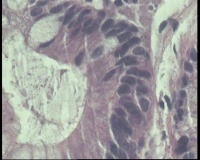

请老师看看胃角溃疡,上皮有轻度非典型增生吗?

性别年龄58岁临床诊断胃角溃疡

一般病史胃角:近后壁见一处圆形溃疡,大小0.6x0.6厘米,底附黄白苔,周围粘膜充血水肿

标本名称胃镜活检

大体所见胃镜活检组织

镜下胃粘膜腺体肠化,局灶腺上皮细胞核大

有坏组织,符合溃疡,腺体肠化,轻度不典型增生。

溃疡+萎缩+肠化+修复。

有肠化和修复性增生。